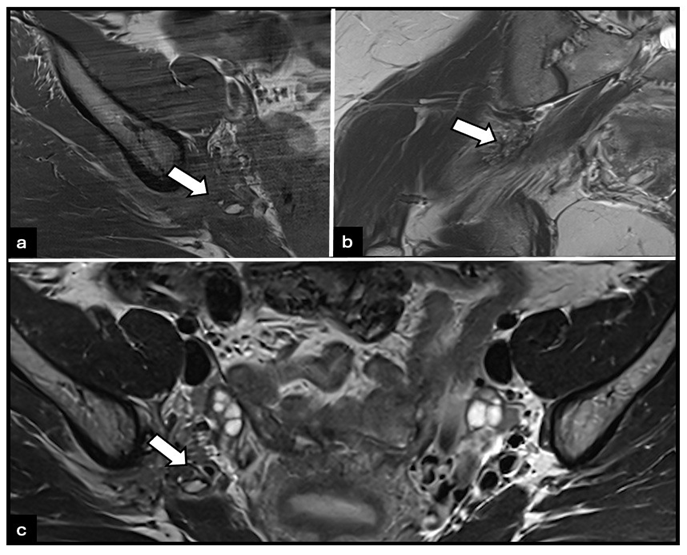

Two main MRI phenotypes are recognized. Fibrous infiltrative lesions appear hypointense on both T1- and T2-weighted sequences and are often associated with deep endometriosis (Figure 4), whereas cystic or hemorrhagic lesions demonstrate hyperintensity on T1- and T2-weighted sequences. Advanced MRI sequences, such as high-resolution 3D T2 and diffusion tensor imaging (DTI), enhance lesion detection and allow visualization of the relationship between endometriotic tissue and nerve fascicles. Accurate imaging is crucial, as nerve-sparing surgery or targeted medical therapy may be required to prevent irreversible neurological deficits [6].

Figure 4: Woman with fibrous infiltrative right sciatic nerve endometriosis. (a) T1-weighted MRI image shows a low-signal-intensity focus along the right sciatic nerve (arrow), consistent with perineural fibrous infiltration. (b) Coronal and (c) axial T2-weighted MRI images demonstrate hypointense infiltrative tissue along the right sciatic nerve (arrows), characteristic of deep endometriosis. No abnormality is observed on the left side.